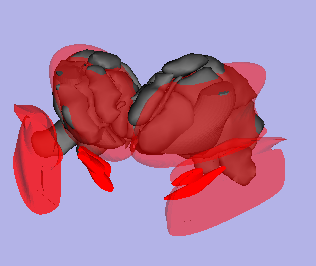

We'll probably need a 2-step registration that first aligns the clipped FOV with the same subjects anatomy reference and then align the latter with the atlas. Once we have good specs for our input data, we can lay down a processing strategy. Masking via a manually defined ROI seems a likely candidate for this problem as well. We are planning to use 3D mean atlas of the thalamus generated from multiple histological data register it with individual Parkinson patient (PD) data, convert using VTK to SPL files and implement into Guideline 4000 electrophysiological workstation.

Our plan for the project week is to register thalamus atlas with individual PD MRI data using Slicer 3.5.